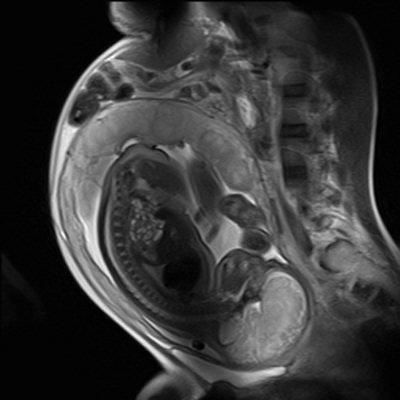

In cases of congenital diaphragmatic hernia, MRI can show herniation of the bowel loops and liver into the left hemithorax, with resultant hypoplasia of the left lung, Hayes noted. In another case of congenital cystic adenomatoid malformation, coronal MRI of a second-trimester fetus showed a large cystic malformation in the right hemithorax, with associated hydrops fetalis. Axial MRI of the thorax showed displacement of the heart, with a hypoplastic left lung.